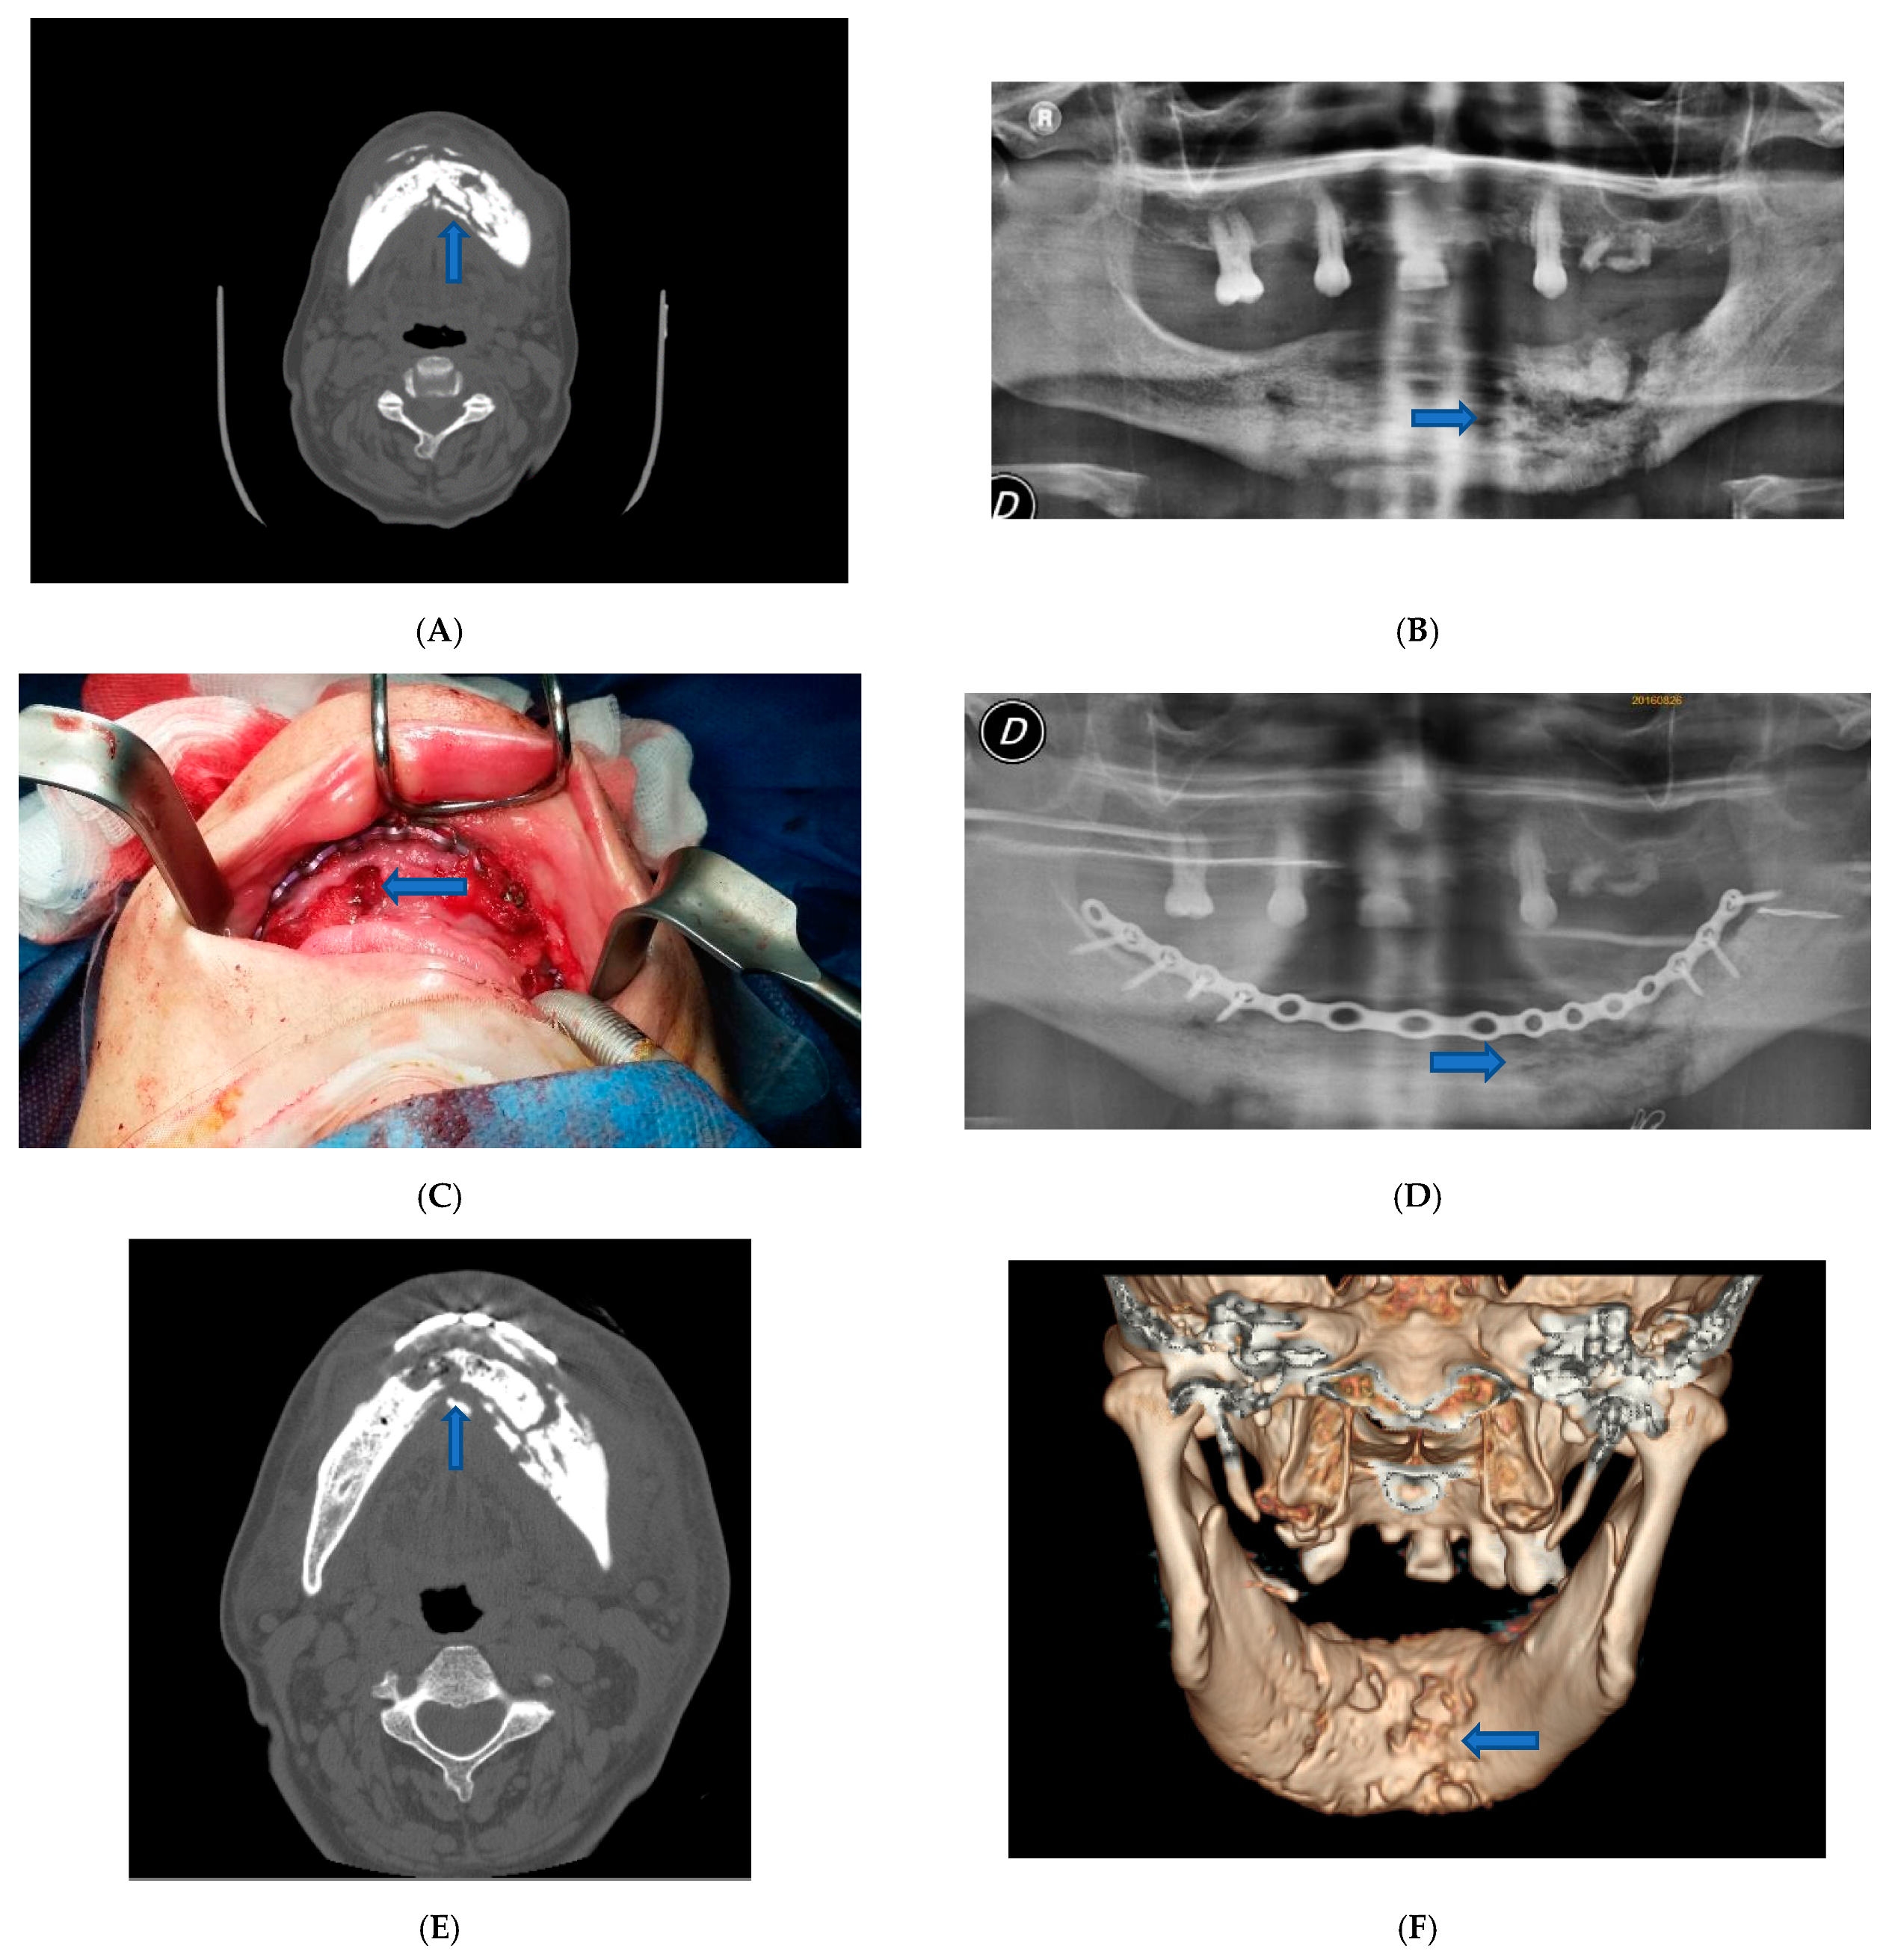

Surgery was performed under general anesthesia. We proceeded to the superficial removal of damaged tissues in the site of the osteonecrosis outbreak to avoid extension of the necrosis and to enhance healing abilities. We eliminated all the necrotic tissue, saving healthy tissue at the excision border to preserve as much as possible mandibular contour aesthetic and function. To stabilize the bone segment, an epi-mucosal fixation was performed using SMART Lock screws and plates without elevation of the mucoperiosteal flap, therefore avoiding any new bone necrosis risk (Figure 1C).

Figure 1.

Patient 1. (A) Pre-operative CT scan image showed lithic area in the mandibular horizontal branches, which appeared subverted and fractured on the left side. (B) Pre-operative panoramic X-ray image of the dental branch revealed lithic area. (C) Epi-mucosal fixation performed using SMART Lock screws and plates without elevating the mucoperiosteal flap. (D) Post-operative panoramic X-ray image of the dental branch. (E) Post-operative CT scan image. (F) Post-operative CT scan 3D reconstruction.

The self-locking screws and plate were inserted before the necrotic bone area resection or sequestrectomy by epi-mucosa plate modelling, positioning and fixing with trans mucosa screw insertion. No need for mucosa incision or periosteal elevation was required at this step of the procedure; the self-locking screws and plate acted as a rigid external fixation system.

The postoperative course was without complications. Postoperative therapy comprised oral hygiene instructions, rinsing with 0.2% chlorhexidine solutions twice a day, and an evening application of 0.2% chlorhexidine gel upon the sutured incision lines, as well as the administration of a non-steroidal anti-inflammatory aid (Ketoprofen 80 mg) for five consecutive days. The patient was also administered antibiotic therapy in the perioperative phase, starting the night before surgery for 4 days, using 500 mg of Amoxicillin and Clavulanate every 8 h. The patient was examined for the first time one week later and then 3 and 6 months after surgery (Figure 1D–F).

For case one, patient physical examination showed no obvious swelling of the face. CT examination showed a lithic area in the mandibular horizontal branches, which appeared subverted and fractured on the left side (Figure 1A). A panoramic X-ray image of the dental arches has revealed the same characteristics (Figure 1B). The alteration was bilateral but particularly accentuated on the left. An additional bone lysis area was also appreciated at the D8 body level. A pathological fracture with radiographic evidence of osteolysis extending to the inferior border of the mandible was compatible with a diagnosis of stage 3 MRONJ caused by the continuous use of denosumab for three years (administration of 1 vial subcutaneous every six months). Additionally, fistulas were present at the lower border of the mandible.